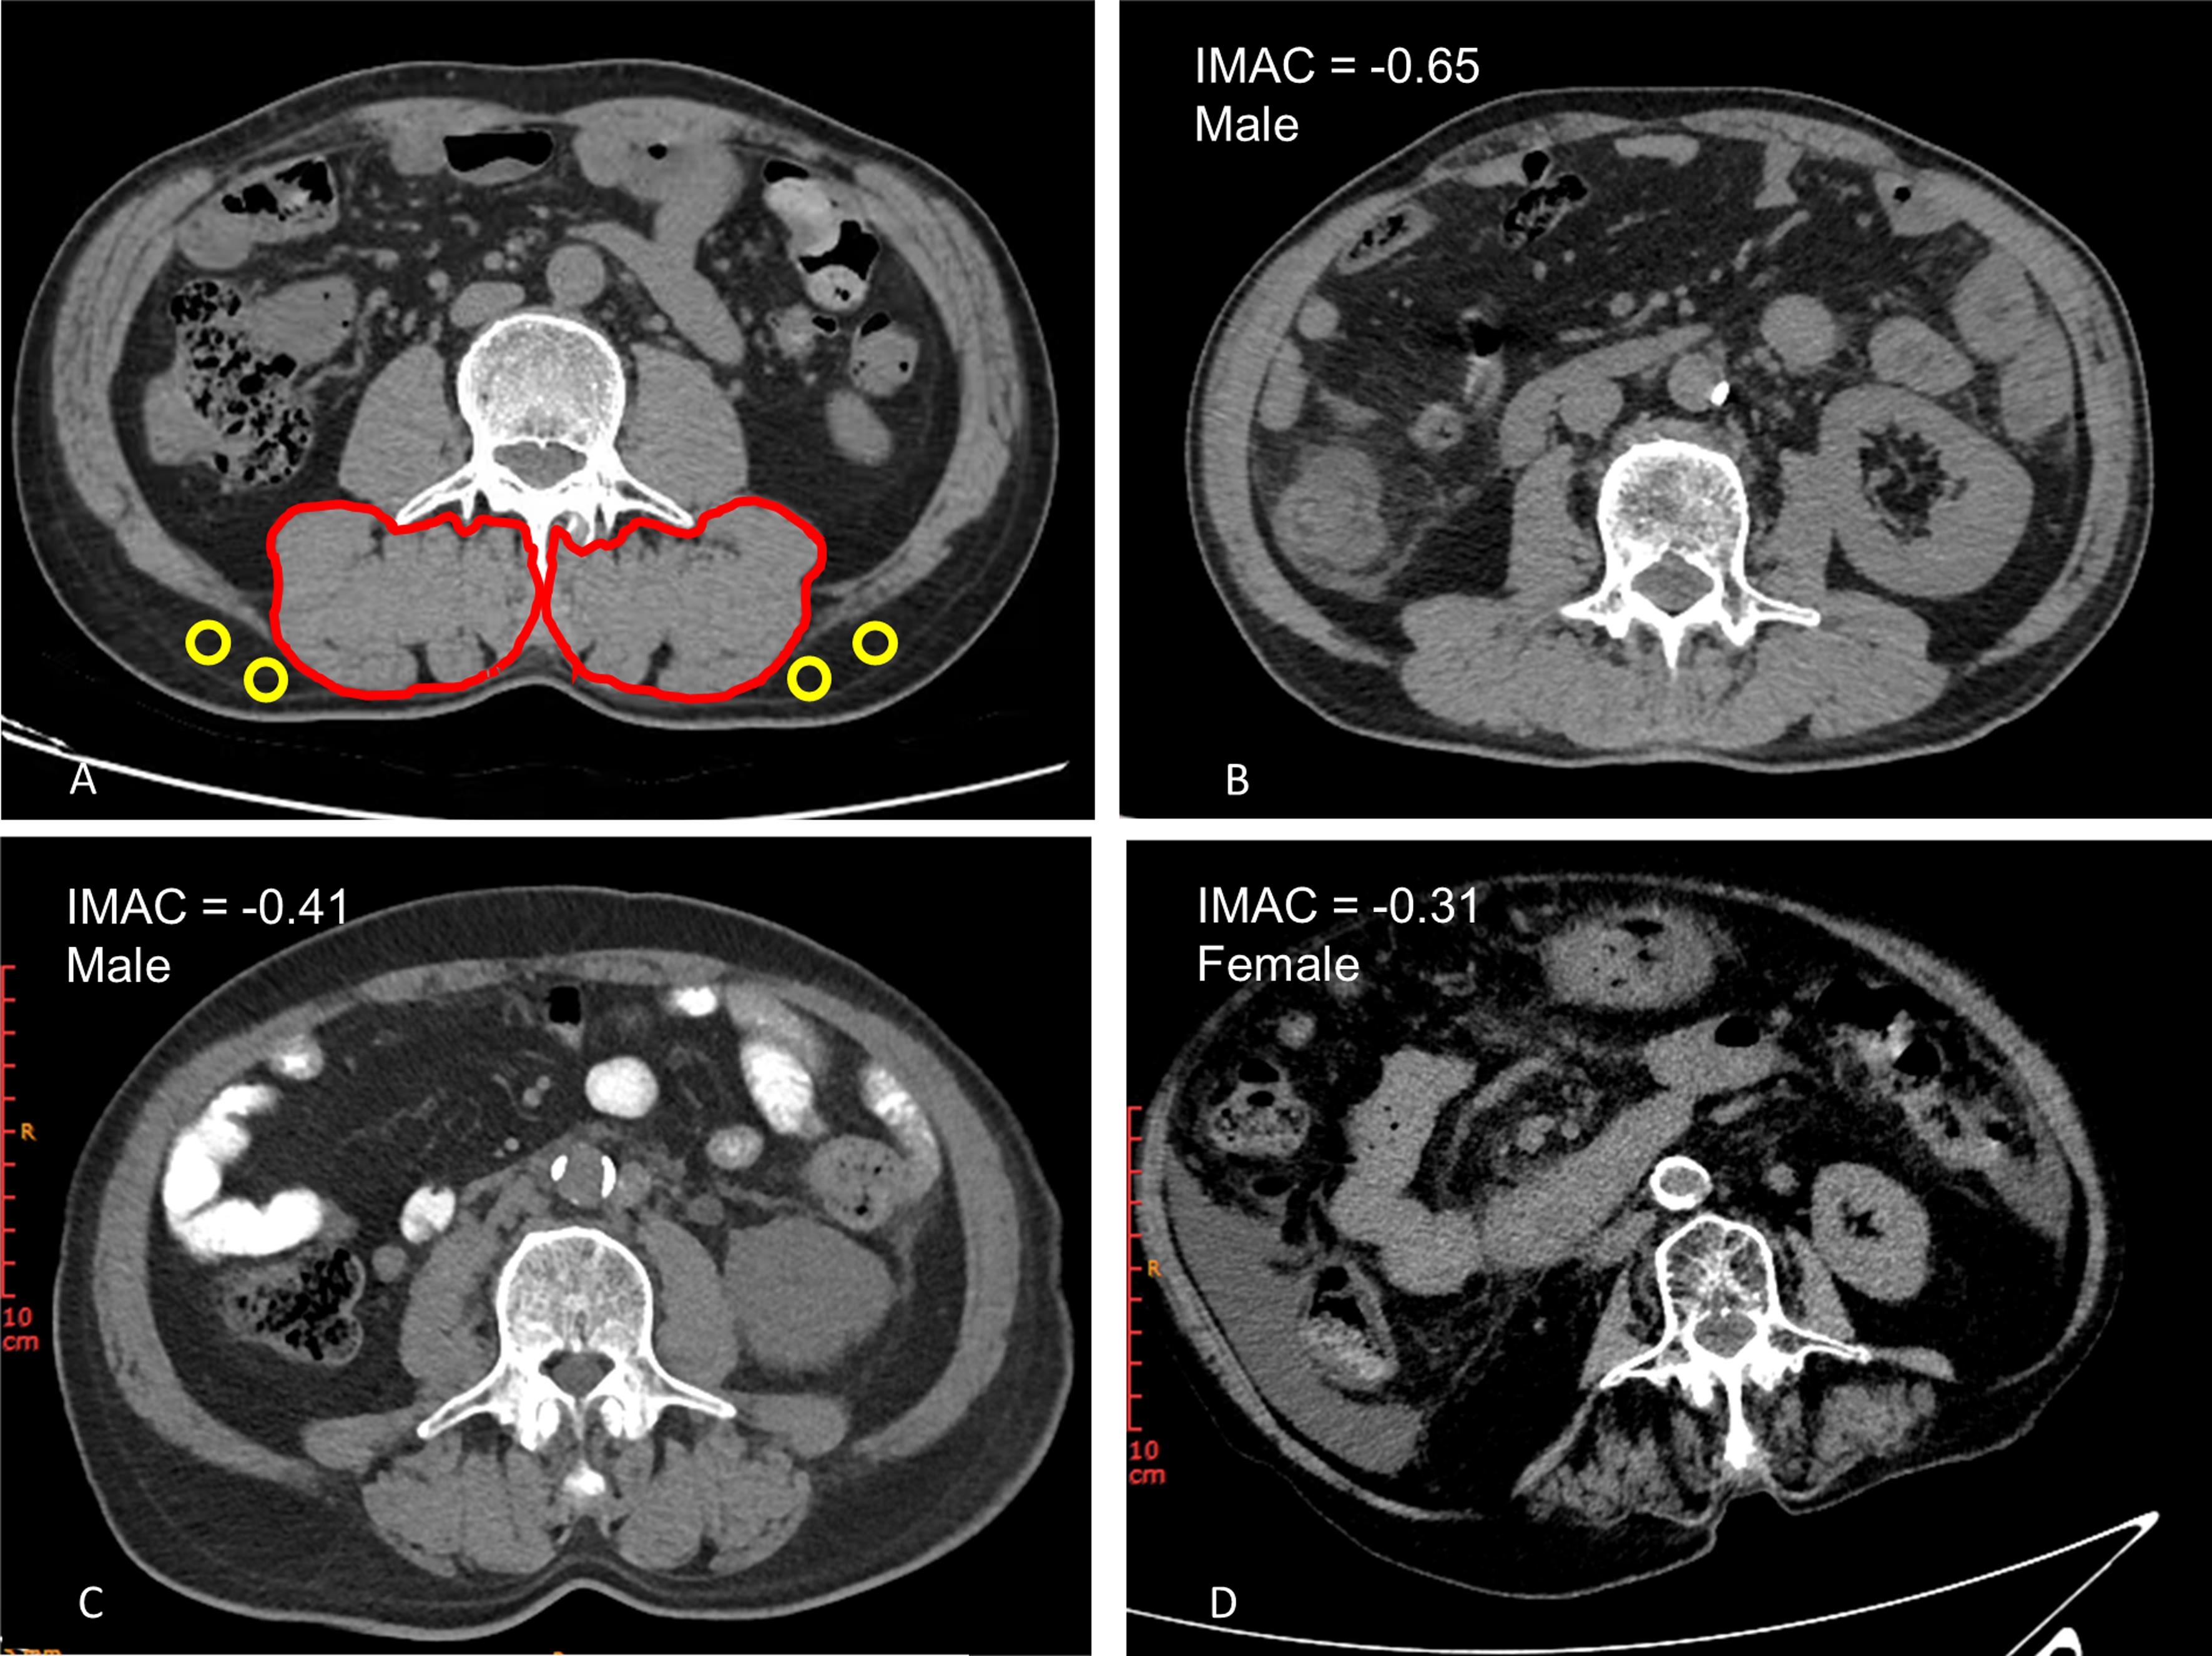

Given the marked prevalence of fluid retention in patients with cirrhosis, the validity and feasibility of these BMI-adjusted cut-offs are ambiguous. Fluid accumulation increases tissue water content, which can artificially lower muscle RA and lead to the overdiagnosis of myosteatosis, as edematous muscle may fall below the standard HU thresholds even without significant fat infiltration. To address this limitation, intramuscular adipose tissue content (IMAC), a novel selection criterion for assessing myosteatosis, has been proposed. IMAC is calculated as the L3 region of interest of the multifidus muscle divided by the region of interest of subcutaneous adipose tissue (Fig. 1).36,37 Accordingly, we utilized IMAC-defined myosteatosis at the L3 level, with cut-offs of >−0.44 and >−0.37 in males and females, respectively.38 It is highlighted that there are other selection criteria or relevant cut-offs to define and diagnose myosteatosis (Table 1).39–44

Abdominal computed tomography images taken at the third lumbar vertebra to quantify intramuscular adipose tissue and muscle radiodensity in patients with cirrhosis.

Fig. 1  Abdominal computed tomography images taken at the third lumbar vertebra to quantify intramuscular adipose tissue and muscle radiodensity in patients with cirrhosis.

(A) Cross-sectional computed tomography image of subfascial muscular tissue in the multifidus muscle (two red circles) and subcutaneous fat (four yellow circles). (B) Cross-sectional computed tomography image for a male patient with IMAC of −0.65. (C) Cross-sectional computed tomography image for a male patient experiencing myosteatosis with IMAC of −0.41. (D) Cross-sectional computed tomography image for a female patient experiencing myosteatosis with IMAC of -0.31. IMAC, intramuscular adipose tissue content.